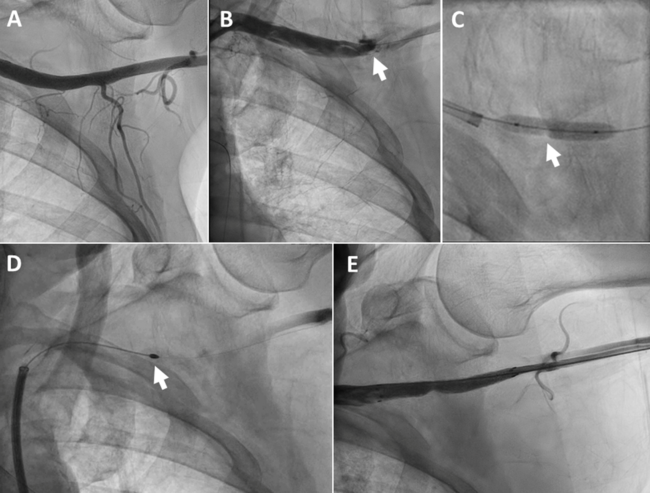

Rotational Atherectomy for Treating Arterial Access-Site Stenosis Caused by Vascular Closure Device Failure Following Transcatheter Aortic Valve Replacement

Video Supplement to "Rotational Atherectomy for Treating Arterial Access-Site Stenosis Caused by Vascular Closure Device Failure Following Transcatheter Aortic Valve Replacement" (Clinical Image).